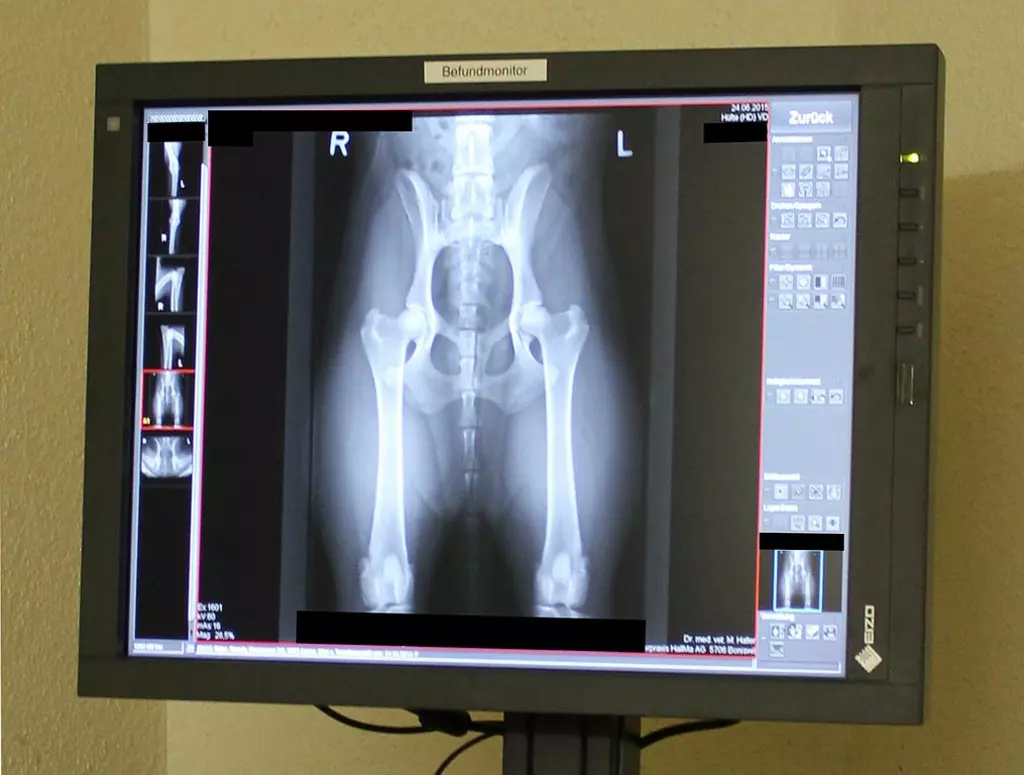

Kleintierpraxis HallMa AG in Boniswil

Suchen Sie eine persönliche und liebevolle Behandlung Ihres Tieres? Dann sind Sie bei uns genau richtig. Wir sind ein familiäres, gut eingespieltes Team, welches sich stets bemu?ht, den Besuch Ihres Vierbeiners in der Kleintierpraxis HallMa so angenehm wie möglich zu gestalten. Durch regelmässige Weiter- und Fortbildungen wird eine zeitgemässe medizinische Versorgung unserer Patienten gewährleistet. Ganz nach dem Motto: Klein aber fein.